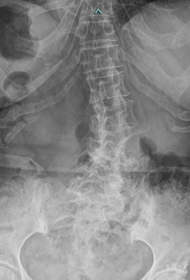

【術前】

第2, 第3, 第4腰椎に前方への変性すべりを認めます。痛みのため背中を反って立てないことが分かります。MRIではいずれの椎間でも強い脊柱管狭窄が発生し、神経が圧迫されているのが分かります。

【術後】

スクリューとロッド、人工骨を使用した手術により腰椎の階段状変性すべりが整復され、痛みが改善したため腰を反って立つことが出来ています。第2腰椎の前方すべりは軽微であったため、金属は使わず除圧術のみに留めています。